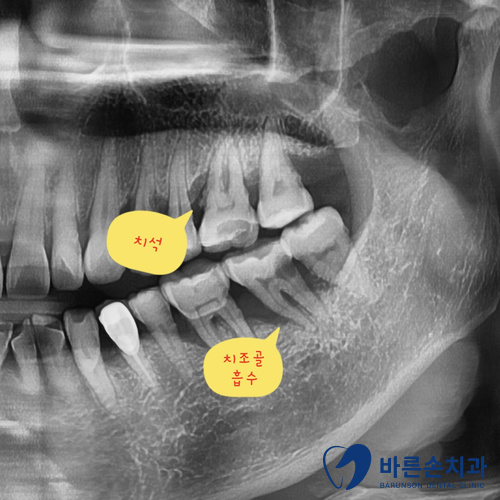

그럼 엑스레이로 상태를 확인해 볼까요?!

1)정상잇몸 사진은 치석이 보이지 않고 치조골(잇몸뼈)이 수평으로 일정하게 이어진 것을 볼 수 있습니다.

2)치주질환 잇몸 사진은 치석이 보이고 치조골 높이가 낮아지면서 잇몸뼈가 수직으로 흡수된 것이 보입니다.

잇몸뼈가 많이 녹을 수록 치아가 많이 흔들리게 되고 이런걸 바로 ‘풍치’ 라고 합니다.

치아가 충치도 없고 건강해도 치아를 잡아주는 잇몸뼈가 약해지면 치아를 뺄 수 밖에 없어집니다.

사진 속 환자분도 결국 발치를 했답니다…너무 안타깝죠ㅠㅠ

치주질환 엑스레이